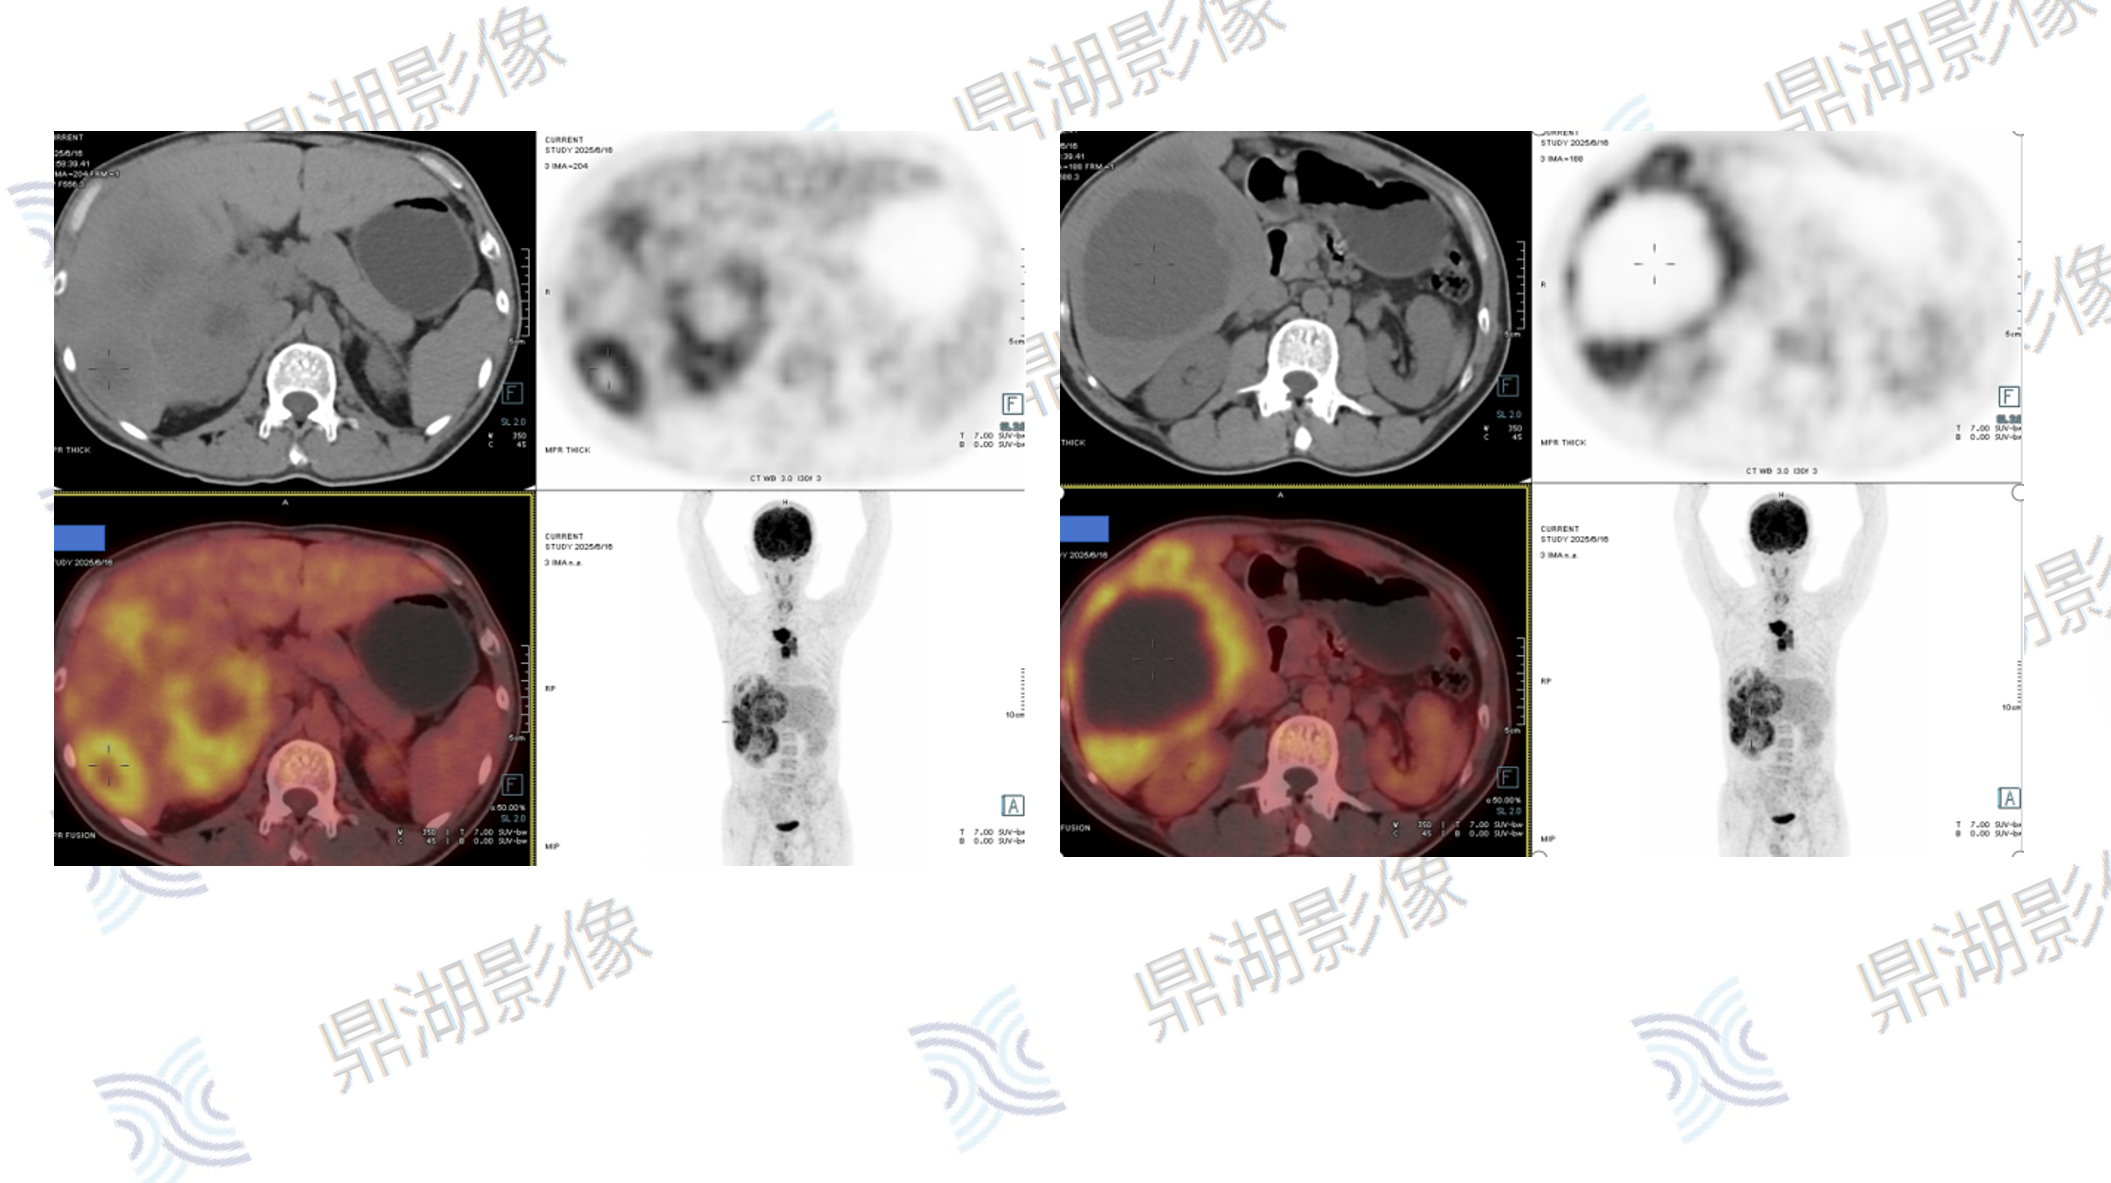

医学影像远程服务